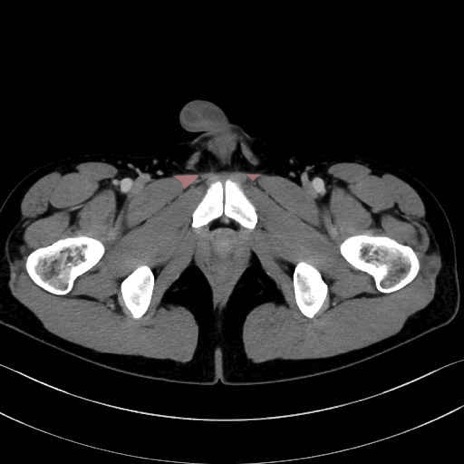

長内転筋(Adductor longus muscle)のCT画像の解剖

長内転筋 (Adductor longus)